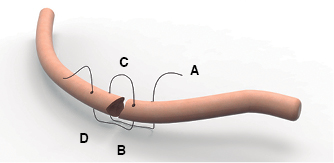

Bajo anestesia general e intubación endotraqueal selectiva se realizó toracotomía posterolateral derecha con apertura del tórax en el 5o espacio intercostal. Se evacuó el hemotórax retenido, luego se practicó decorticación pleural visceral y parietal y finalmente, se procedió a la osteosíntesis de los arcos costales fracturados que provocaron la deformidad con hundimiento de la parrilla costal y lesión del parénquima pulmonar por los extremos de las costillas con proyección intratorácica. Cada foco de fractura fue expuesto levantando el periostio adyacente a la línea de fractura. Se perforó cada arco costal fracturado con un taladro eléctrico y brocas de 2 mm en dos puntos equidistantes en cada extremo del segmento fracturado. Los agujeros se trepanaron a 10 mm de los bordes fracturados con separación de 10 mm, uno por detrás del otro, pero en diferentes líneas (Figura 3). Se pasó el alambre (material sutura no absorbible monofilamento #5 Ethi-Pack, Ethicon) del agujero más lejano (A) de fuera adentro, al más corto (C) de dentro afuera y del corto (B) de fuera adentro; al más lejos (D) de dentro afuera; cerrándolo en la cara externa de la costilla (Figura 4). Usamos un Angiocath # 16 como facilitador del paso del alambre, cuando se pasa del espacio intratorácico hacia el exterior.

Figura 3: Se pasa el alambre el agujero más lejano (A) de fuera adentro, al más corto (C) de dentro afuera y del corto (B) de fuera adentro; al más lejos (D) de dentro afuera.

Para la fijación costal se han descrito diferentes dispositivos y técnicas como suturas de alambre, intramedulares de Kirschner,10 grapas de Judet y las placas hechas de varios metales o materiales absorbibles. También, se han descrito técnicas mínimamente invasivas,12,13 fijaciones internas para lesiones anteriores con fracturas cartilaginosas14 y utilización de la barra de Nuss para estabilización de tórax batiente severo con lesión bilateral de la parrilla costal.15 La fijación quirúrgica con placas y tornillos bicorticales bloqueados, es considerada la técnica contra la cual deben ser comparadas las nuevas.8 El titanio es el metal aconsejable como material de osteosíntesis debido a su biocompatibilidad y resistencia a la corrosión; por lo que tanto los sistema Stratos, Stracos6-9 y MatrixRIB16,17 lo utilizan. Desgraciadamente, su alto costo representa una limitante para su uso. Es por ello que hemos desarrollado un método de estabilización de fracturas costales utilizando alambre monofilamento, con un sistema de fijación de cuatro orificios perforados, dos en cada extremo de los segmentos de la costilla fracturada, uno proximal a 10 mm del borde y otro distal a 10 mm del primero; pero en diferentes líneas de perforación. Esto tiene como propósito evitar la pérdida de tensión por debilitamiento de las corticales, la lesión por compresión del paquete vasculonervioso y conseguir la estabilidad del foco de fractura, aplicando el principio de lejos cerca-cerca lejos. El resultado final es lograr dos líneas paralelas de alambre en sentido vertical al eje de la costilla en su cara interna y que queden entrecruzados en su cara externa. Esto permite una buena alineación de los segmentos costales, el levantamiento de la pared y la firmeza de la parrilla costal.